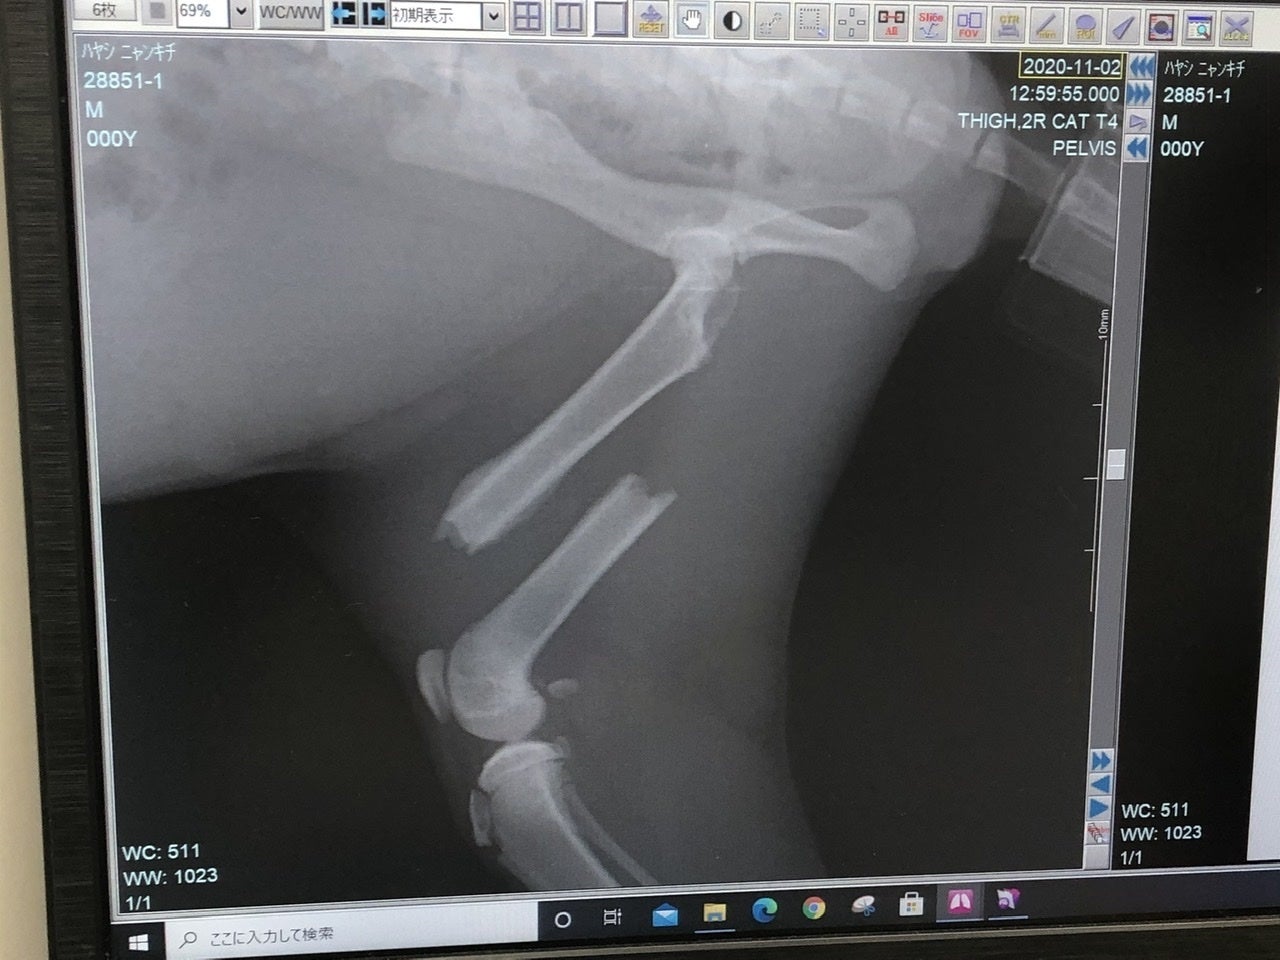

「右上腕部末端(肘)骨折」

「右後ろ大腿骨(付根)骨折」

の2箇所が骨折していました。

それ以外のキズや臓器系、病気などは無く、強い衝撃が生後間もなく右半分に当たり、骨折したものだと、先生がおっしゃられていました。

現在は3カ月ぐらいで、時間の経過と共に骨折した周りの肉(繊維)が固まってきているとの事です。(一度固まった肉を削いで、骨を戻し、金具を入れる)

再度診察の結果、「右上腕部末端(肘)」が、折れた骨の周辺の肉(繊維)が固まってきており、神経が多く通ってる箇所なんで、逆に傷つける恐れがあるとの事で、今回は見送られました。徐々にですが体重もかけれるのと、後ろが治れば負担も少なくなるとの見解です。

「右後ろ大腿骨(付根)」は肉を剥がして奥まで入った骨を戻し、固定の金具をつけます。